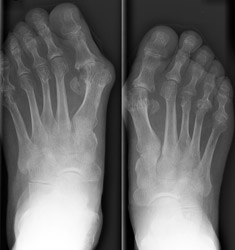

2. Erosion pattern:

Early erosive changes are seen involving the "bare areas" of

metatarsal heads. In late stages of RA, subluxations may occur at the MTP

joints with the proximal phalanges subluxating in fibular direction and metatarsal

heads subluxating in plantar direction. Tarsal bones are involved as a unit

with uniform joint space loss. Bony ankylosis of tarsal bones may occur. In

3. Differential diagnosis:

The absence

of bone proliferation and bony ankylosis, and the presence of osteoporosis are

common finding of rheumatoid arthritis and are useful in the differentiation

of rheumatoid arthritis from seronegative arthritis.